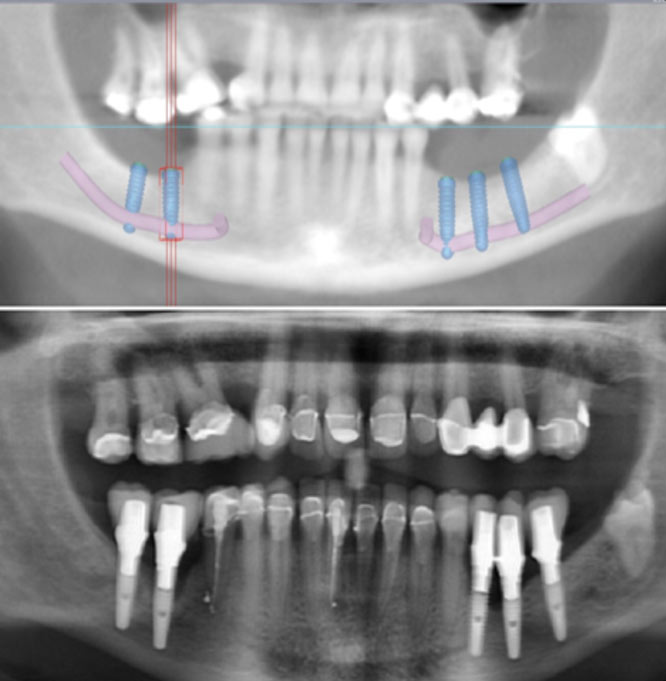

Nerve Laterilsation

Where the back teeth were lost a long time ago and the bone that was around the teeth has shrunk, and you need to place dental implants where there is inadequate bone above the nerve. By moving the “cable” of the nerve of the lower jaw to the side, the bone below can be used also for implant placement to engage adequate bone volume.